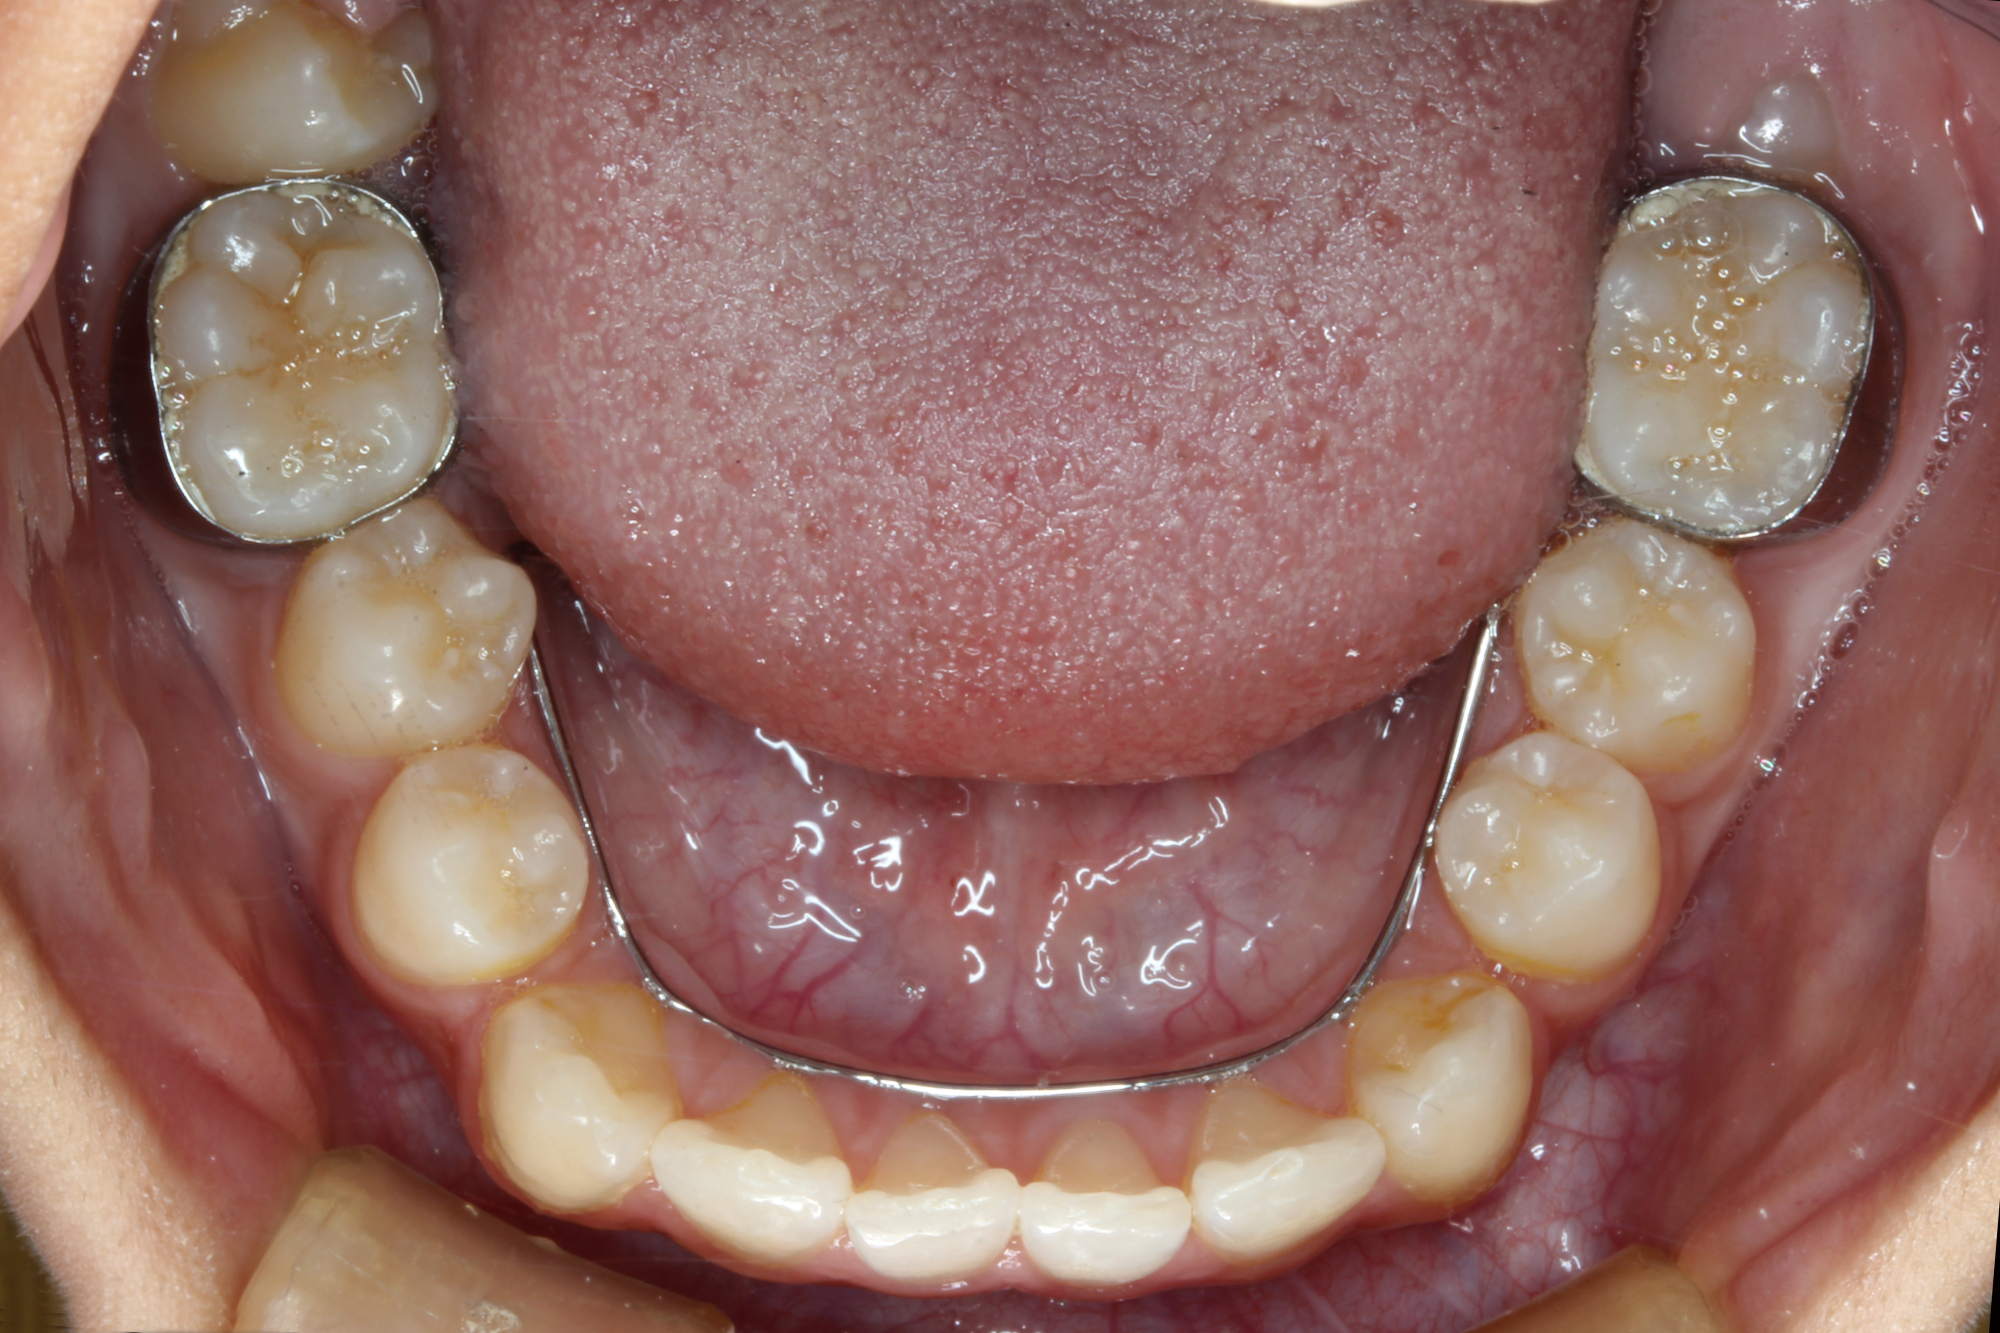

日本で行われている拡大床治療にも色々な方法がありますが当院での特長は最初に永久歯に生え替わる上下4本の前歯を奥歯の生え替わりが始まる前までに顎を拡大してきれいに並べることです。そのため拡大床治療の期間は小学校1年生頃から4、5年生頃までの間に限定しており、それまでに目的が達成できない場合には別の治療法に移行します。またゆっくりスペースを獲得するようにしているのも特長で2週間に1回ネジを回すようにしています。一般的には1週間にⅠ回ないし2回ネジを回すことが多いようです。ゆっくり進めるので一日の装着時間はお家にいるときと寝ている間だけにしています。学校や自宅以外での装着はせずゆっくり拡大していくので治療期間が長くなりますが後戻りは少なく確実になります。治療開始時期が大切ですので時期を逸した場合には拡大床治療は行いません。一般的に拡大床治療の評判が悪いのは開始時期が遅く、いつまでも治療を長引かせ治らないことによるものが多いようです。 拡大床治療はスペースを作って永久歯がならぶスペースを作ることが目標ですので細かい歯の向きや角度まで整えられないこともあります。そんな場合には別の矯正治療が必要になります。

拡大床治療で顎のスペースを拡げられるのは11歳くらいまでです。そのため個人差はありますが遅くても小学校2年生までに始めなければなりません。下の前歯が生え替わりはじめた頃から下の前歯が4本、上の前歯が2本生え替わる頃までが始め時です。すでに上下4本とも生え替わってしまった場合にはすでに遅いことが多くあります。